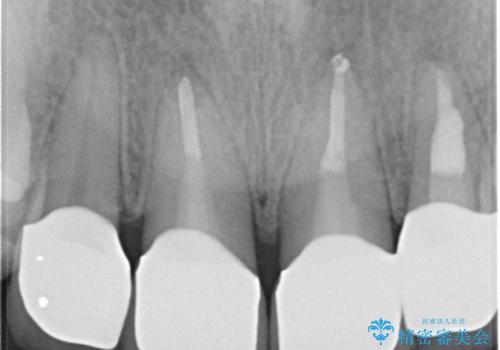

自然な前歯にしたい ジルコニアクラウンでの修復

- 前歯を綺麗にしたいとのことで来院されました。

色調・適合ともに改善するために一度被せ物を外し、歯の形を整えた後に新しい被せ物を装着していきます。

- 右上12左上12/仮歯4本+ジルコニアクラウン4本:44,000+484,000円 左上2/根管治療(保険)費用は治療当時の料金となります